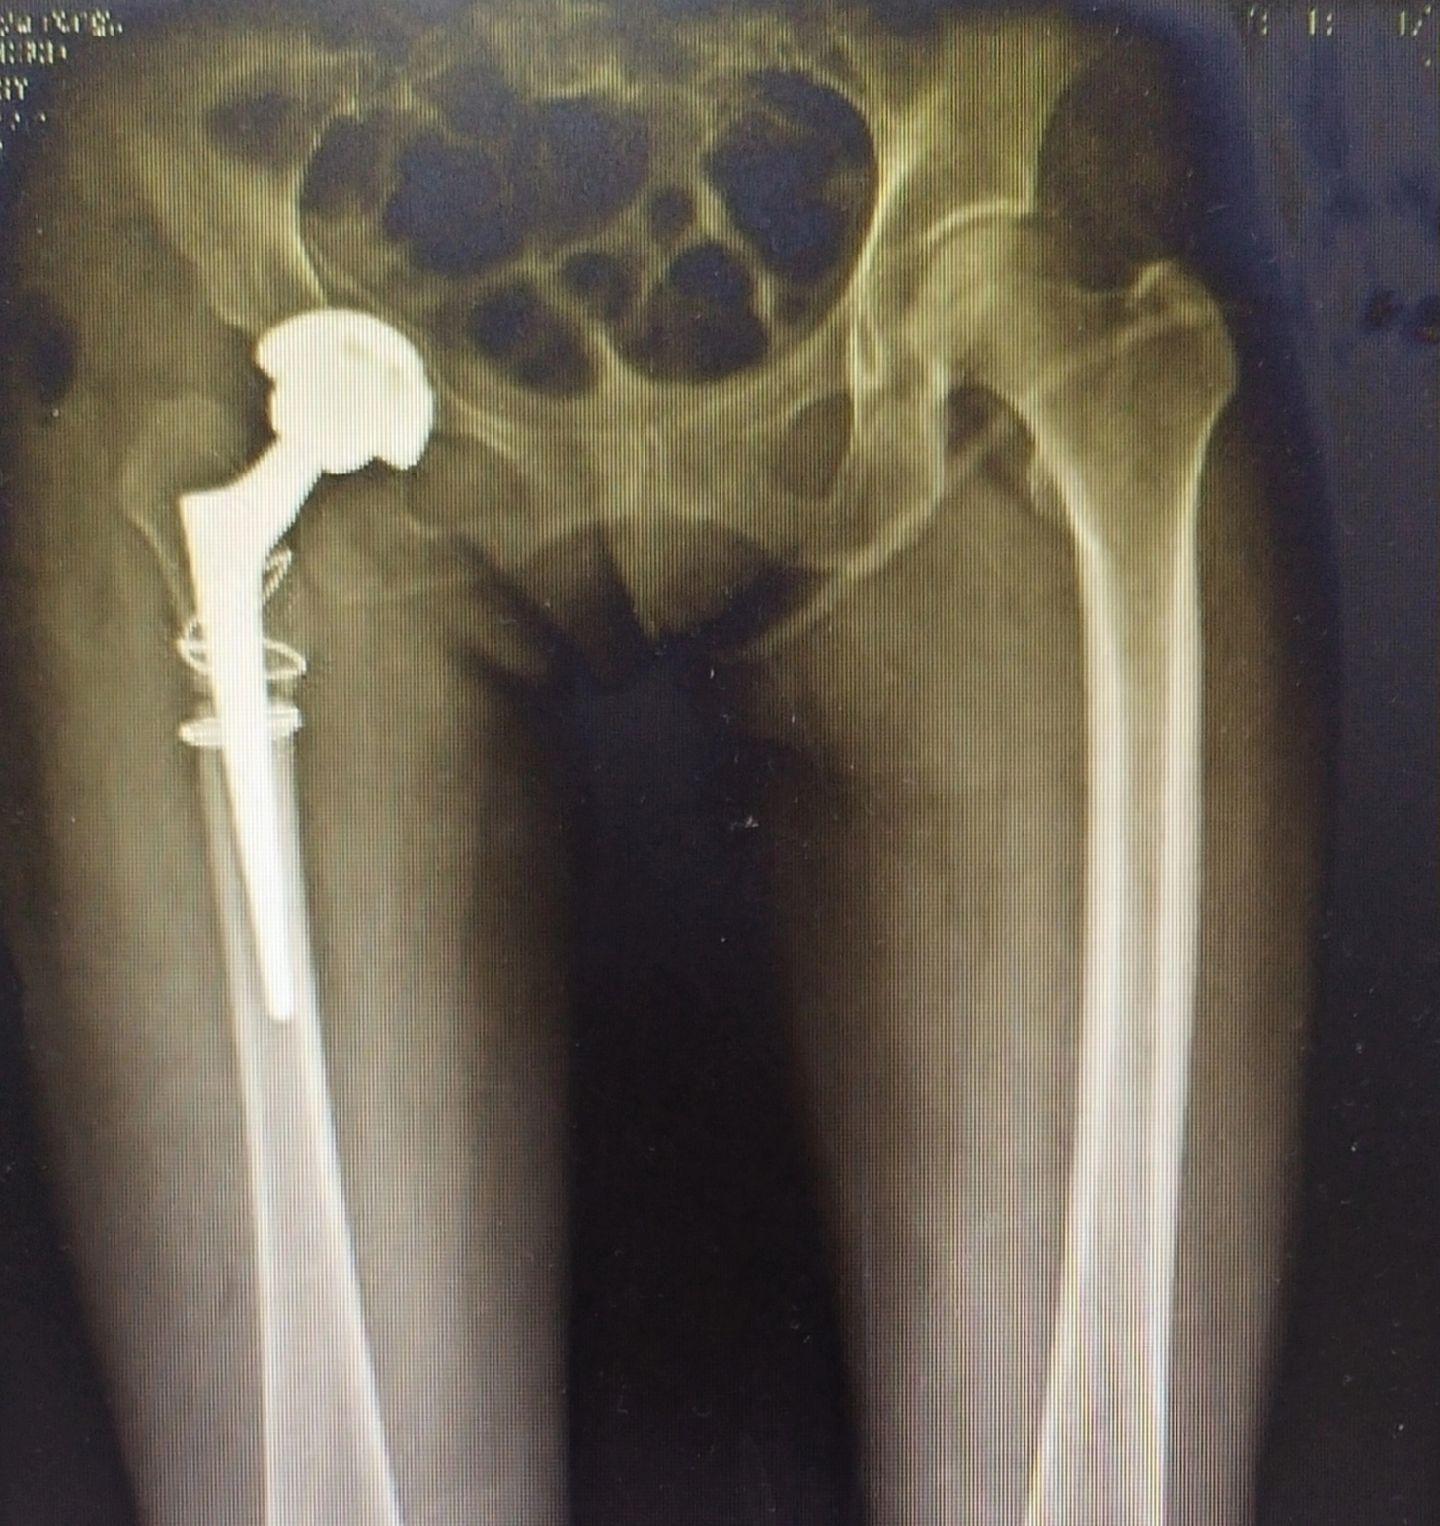

髋关节置换。DDH(先天性髋关节发育不良)四型高脱,要乐观,相信目前的技术,要有信心🌹